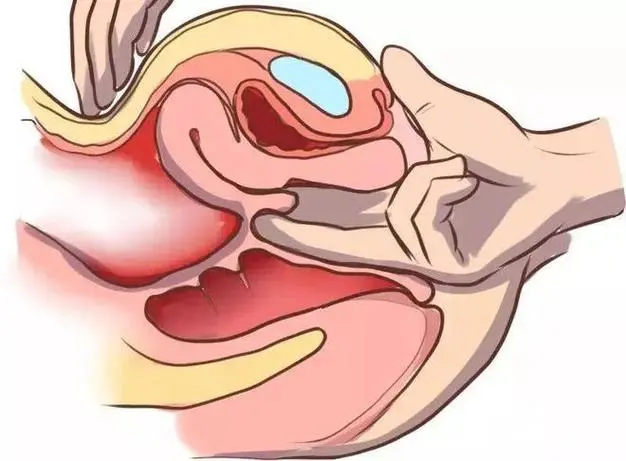

阴道长度在性行为、分娩等因素的影响下可能会发生一定的改变。例如,在分娩过程中,由于子宫收缩,阴道会逐渐扩张,以便让胎儿通过。

阴道是非常柔软和具有弹性的组织,这使得它能够适应各种生理需求。它可以自然扩张以适应性交、分娩等过程。有时候,阴道长度过长或过短可能会给女性带来身体上的不适。这种情况需要医生进行评估和治疗。